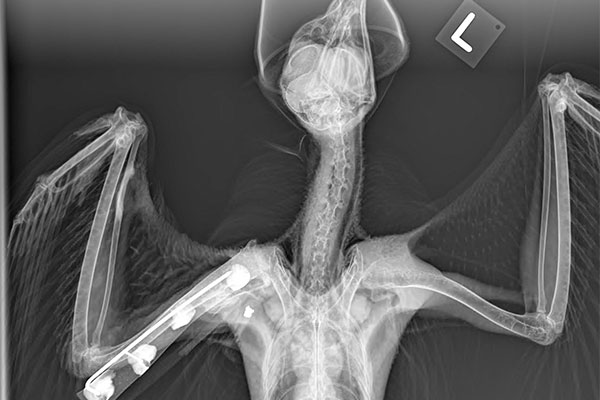

radiograph of a birdDiagnostic Imaging